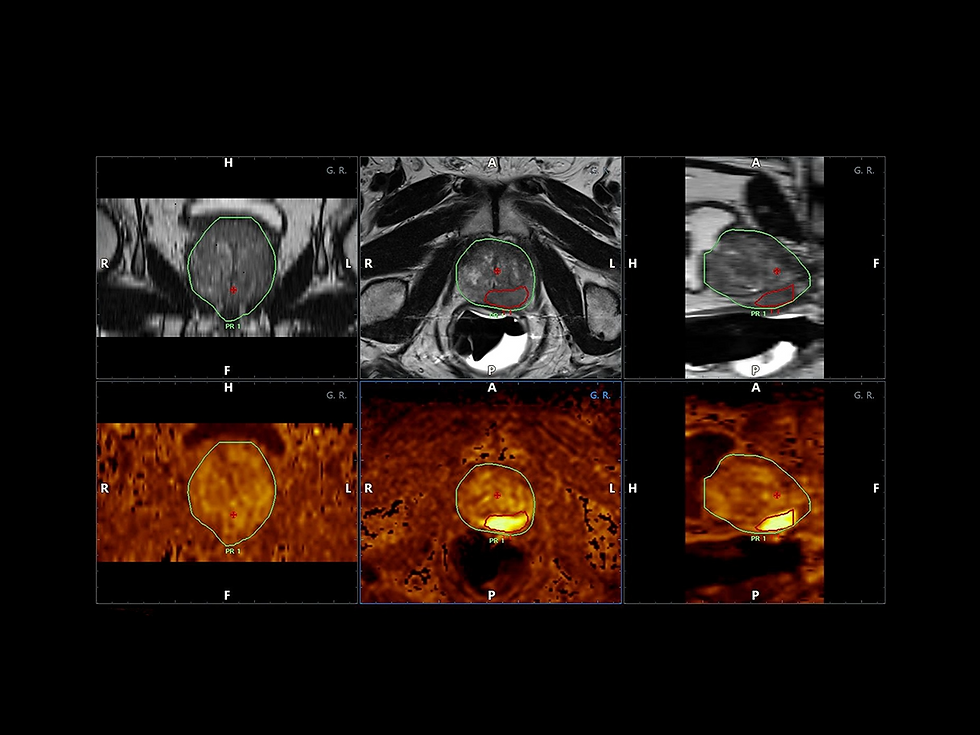

UroFuzija - Najpreciznije biopsije prostate kao rezultat spoja Magnetne rezonance i Ultrazvuka

Iskusni radiolozi i početnici sada postižu jednako visok stepen preciznosti koristeći UroFuziju, Esaote-ovo najsavremenije rešenje za dijagnostičko snimanje koje maksimalno koristi kombinaciju Ultrazvuka i MR ili PET modaliteta.

Korišćenjem tehnologije Augmented Insight™ (A.I.), poboljšava se efikasnost radnog procesa automatizacijom MR konturisanja i segmentacije prostate sa trenutnom i automatskom UZ-MR sinhronizacijom, primenjenom i na transperinealne (TPUS) i transrektalne (TRUS) pristupe biopsiji prostate.

UroFuzija nudi mogućnost jednostavnog kombinovanja različitih mpMRI serija, olakšavajući identifikaciju sumnjivih lezija prostate.